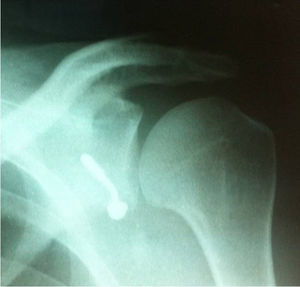

El corte de la coracoides se realiza con sierra, mientras se sostiene la coracoides, se abduce y rota externamente la extremidad, y se libera el ligamento coracohumeral. Al voltearse, se deja en sentido superficial la cara profunda y, con ayuda de la sierra, se decortica. En este momento se realizan los orificios con broca de 3,2 en sentido perpendicular al eje longitudinal y centrados en cuanto a su espesor, y se limpian los bordes. Se lleva el brazo en rotación neutra y se deja la coracoides debajo del separador que sostiene el pectoral mayor. Una vez que se han identificado los márgenes superior e inferior, se divide el músculo subescapular en línea con las fibras en la unión del tercio medio e inferior con ayuda de unas tijeras de Mayo. Si el paciente es laxo, puede efectuarse en la unión de la mitad superior y la mitad inferior. Se separan los bordes y se deja el inferior en sentido medial y se expone la cápsula, lo que disminuye la rotación externa para mejorar la visibilidad. Se realiza una incisión de 1 cm en sentido vertical en la cápsula a la altura de la articulación, se visualiza el cartílago y se coloca un retractor de la cabeza humeral dentro de la articulación; se coloca un retractor de Hohmann en el borde inferior del cuello glenoideo y se expone la glenoides. Se secciona el rodete con electrocauterio, que se inicia desde la posición lateral, se extiende 2 cm en sentido medial y luego 3 cm en sentido superior, y de nuevo en sentido lateral, con lo cual se configura una «U», se extrae el rodete y se expone la lesión de Bankart. Con un osteótomo o una gubia se retira el rodete, la lesión de Bankart y el periostio, y se raspa dejando sangrante el hueso para estimular la incorporación de la coracoides. Se realizan los orificios con broca a las 5 horas de reloj en el hombro derecho a 7 mm en sentido medial al borde articular glenoideo. Ello varía de acuerdo con el tamaño de la coracoides. Se mide la profundidad del orificio y se le suma la del proceso coracoideo que normalmente debe dar un total entre 30 y 40 mm. Se lleva la coracoides a su posición, que debe quedar de 2 a 4 mm en sentido medial al borde glenoideo y se fija con uno o dos tornillos (fig. 3).

Estos pueden ser maleolares de rosca parcial paralelos o máximo a 15° divergentes de la glenoides, mientras que debe ajustarse de forma adecuada la orientación y dejar la coracoides en continuidad con la superficie articular o en sentido muy ligeramente medial, nunca lateral (fig. 4).

ResultadosSe procedió a intervenir a 18 pacientes mediante cirugía de Latarjet entre marzo de 2010 y marzo de 2012; 14 (77%) eran hombres. El promedio de edad fue 34,5 años, el individuo con mayor edad tenía 51 años y el menor, 21 años. Todos los pacientes practicaban algún deporte, de acuerdo con la entrevista realizada. Sin embargo, solamente el 50% lo hacía de forma competitiva; asociado con esta frecuencia de práctica, 11 (61,1%) realizaban deportes que implicaban contacto físico, el cual aumentaba en su intensidad dependiendo del deporte (tabla 1). Todos los individuos presentaron lesión ósea; 8 (44,4%), lesión humeral (Hill-Sachs) y 10 (55,4%), lesión del reborde glenoideo y lesión de Hill-Sachs. De los 18 pacientes, 4 (22,2%) refirieron episodios quirúrgicos previos, que iban desde lesión de Bankart artroscópica hasta cirugía abierta, los cuales se confirmaron por revisión de historias clínicas. En cuanto a la hiperlaxitud, 13 pacientes (72,2%) la presentaban, lo cual se tuvo en cuenta para los criterios de acuerdo con la puntuación del ISIS (fig. 5).

Se presentó una complicación postoperatoria (lesión del nervio axilar. Dos pacientes consultaron posteriormente por nuevo traumatismo; uno de ellos consultó por accidente de tránsito, el cual persistía con luxaciones recidivantes. El otro presentó una caída de altura con dolor residual y en las radiografías se podía apreciar seudoartrosis. Este paciente, en el momento de la evaluación, se encontraba asintomático; el tercer paciente presentó una lesión parcial del nervio axilar con reinervación.

| Masc | 51 | 2 | Contacto | Competición | Sí | 8 | 2 | Humeral | Retorno deportivo; no volvió a presentar luxaciones, pero en el control radiográfico al año se puso de manifiesto tornillo doblado (fig. 6) |